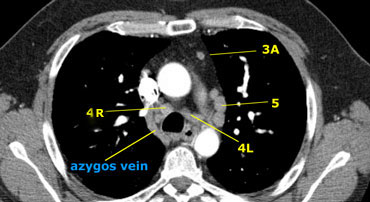

On the left an image just above the level of the pulmonary trunk demonstrating lower paratracheal nodes on the left and on the right.

In addition there are also station 3 and 5 nodes.

On the left an image at the level of the lower trachea just above the carina.

To the left of the trachea 4L nodes.

Notice that these 4L nodes are between the pulmonary trunk and the aorta, but are not located in the AP-window, because they lie medially to the ligamentum arteriosum.

The node lateral to the pulmonary trunk is a station 5 node.